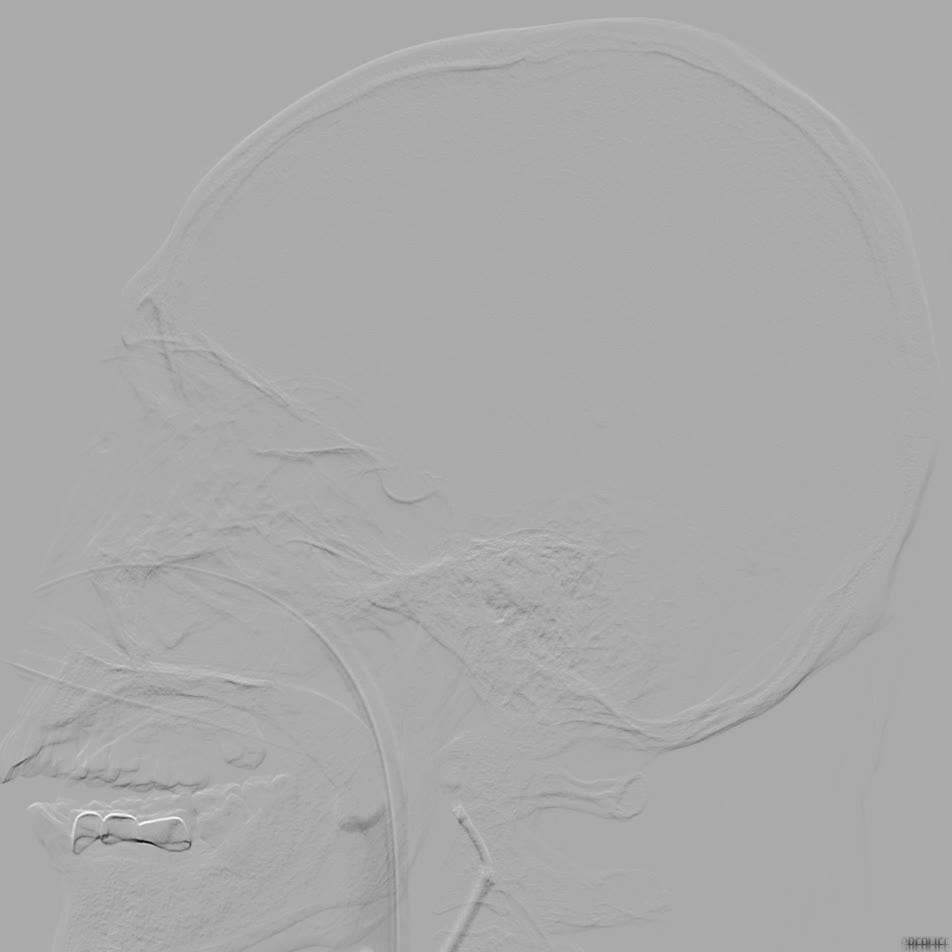

NeuroHawk Case 7